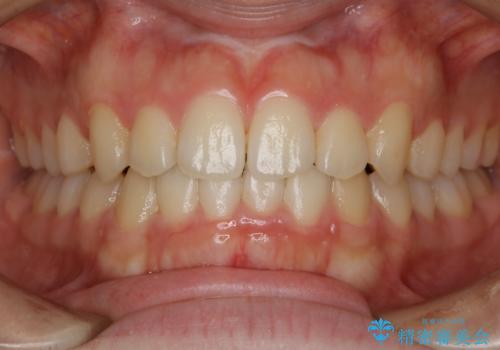

- 上の前歯のすきっ歯と下の前歯のガタつきを主訴にご来院されました。

噛み合わせの改善も同時に進めつつ、主訴の部分も効率的に治していくためマウスピース装置でゴムかけを行いながら治療を進めていきました。

正中離開(すきっ歯)

真ん中の歯が左右に開いてしまい隙間ができてしまう状態を「正中離開」といい、俗にすきっ歯と呼ばれています。

隙間を埋めていく方向に歯を移動させることで改善していくケースが多く、比較的治りやすい不正咬合のひとつとされています。

しかしながら、歯が捻じれていたり、噛み合う歯との位置関係によっては治療が難しくなる場合があります。